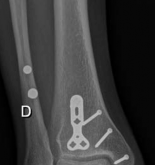

A 53-year old man injured his right ankle in a motor vehicle accident. Clinical examination revealed a swollen and painful right ankle. It was a closed injury. X-rays revealed a fracture dislocation of the distal tibia with partial articular involvement (AO/OTA 43B3), and associated fracture of the fibula above

the level of the syndesmosis (Fig 2.3-1). A computed tomographic (CT) scan showed a fracture of the posterior tibial plafond with the fracture line extending from midline of the medial malleolus into the incisura fibularis, with impaction and incarceration of joint fragments (Fig 2.3-2).

Fig 2.3-1a–b Immediate postinjury x-rays. - AP x-ray showing the characteristic medial malleolar double contour sign.

- Lateral x-ray showing a displaced partial articular fracture of the posterior distal tibia (AO/OTA 43B3) with tibiotalar dislocation.